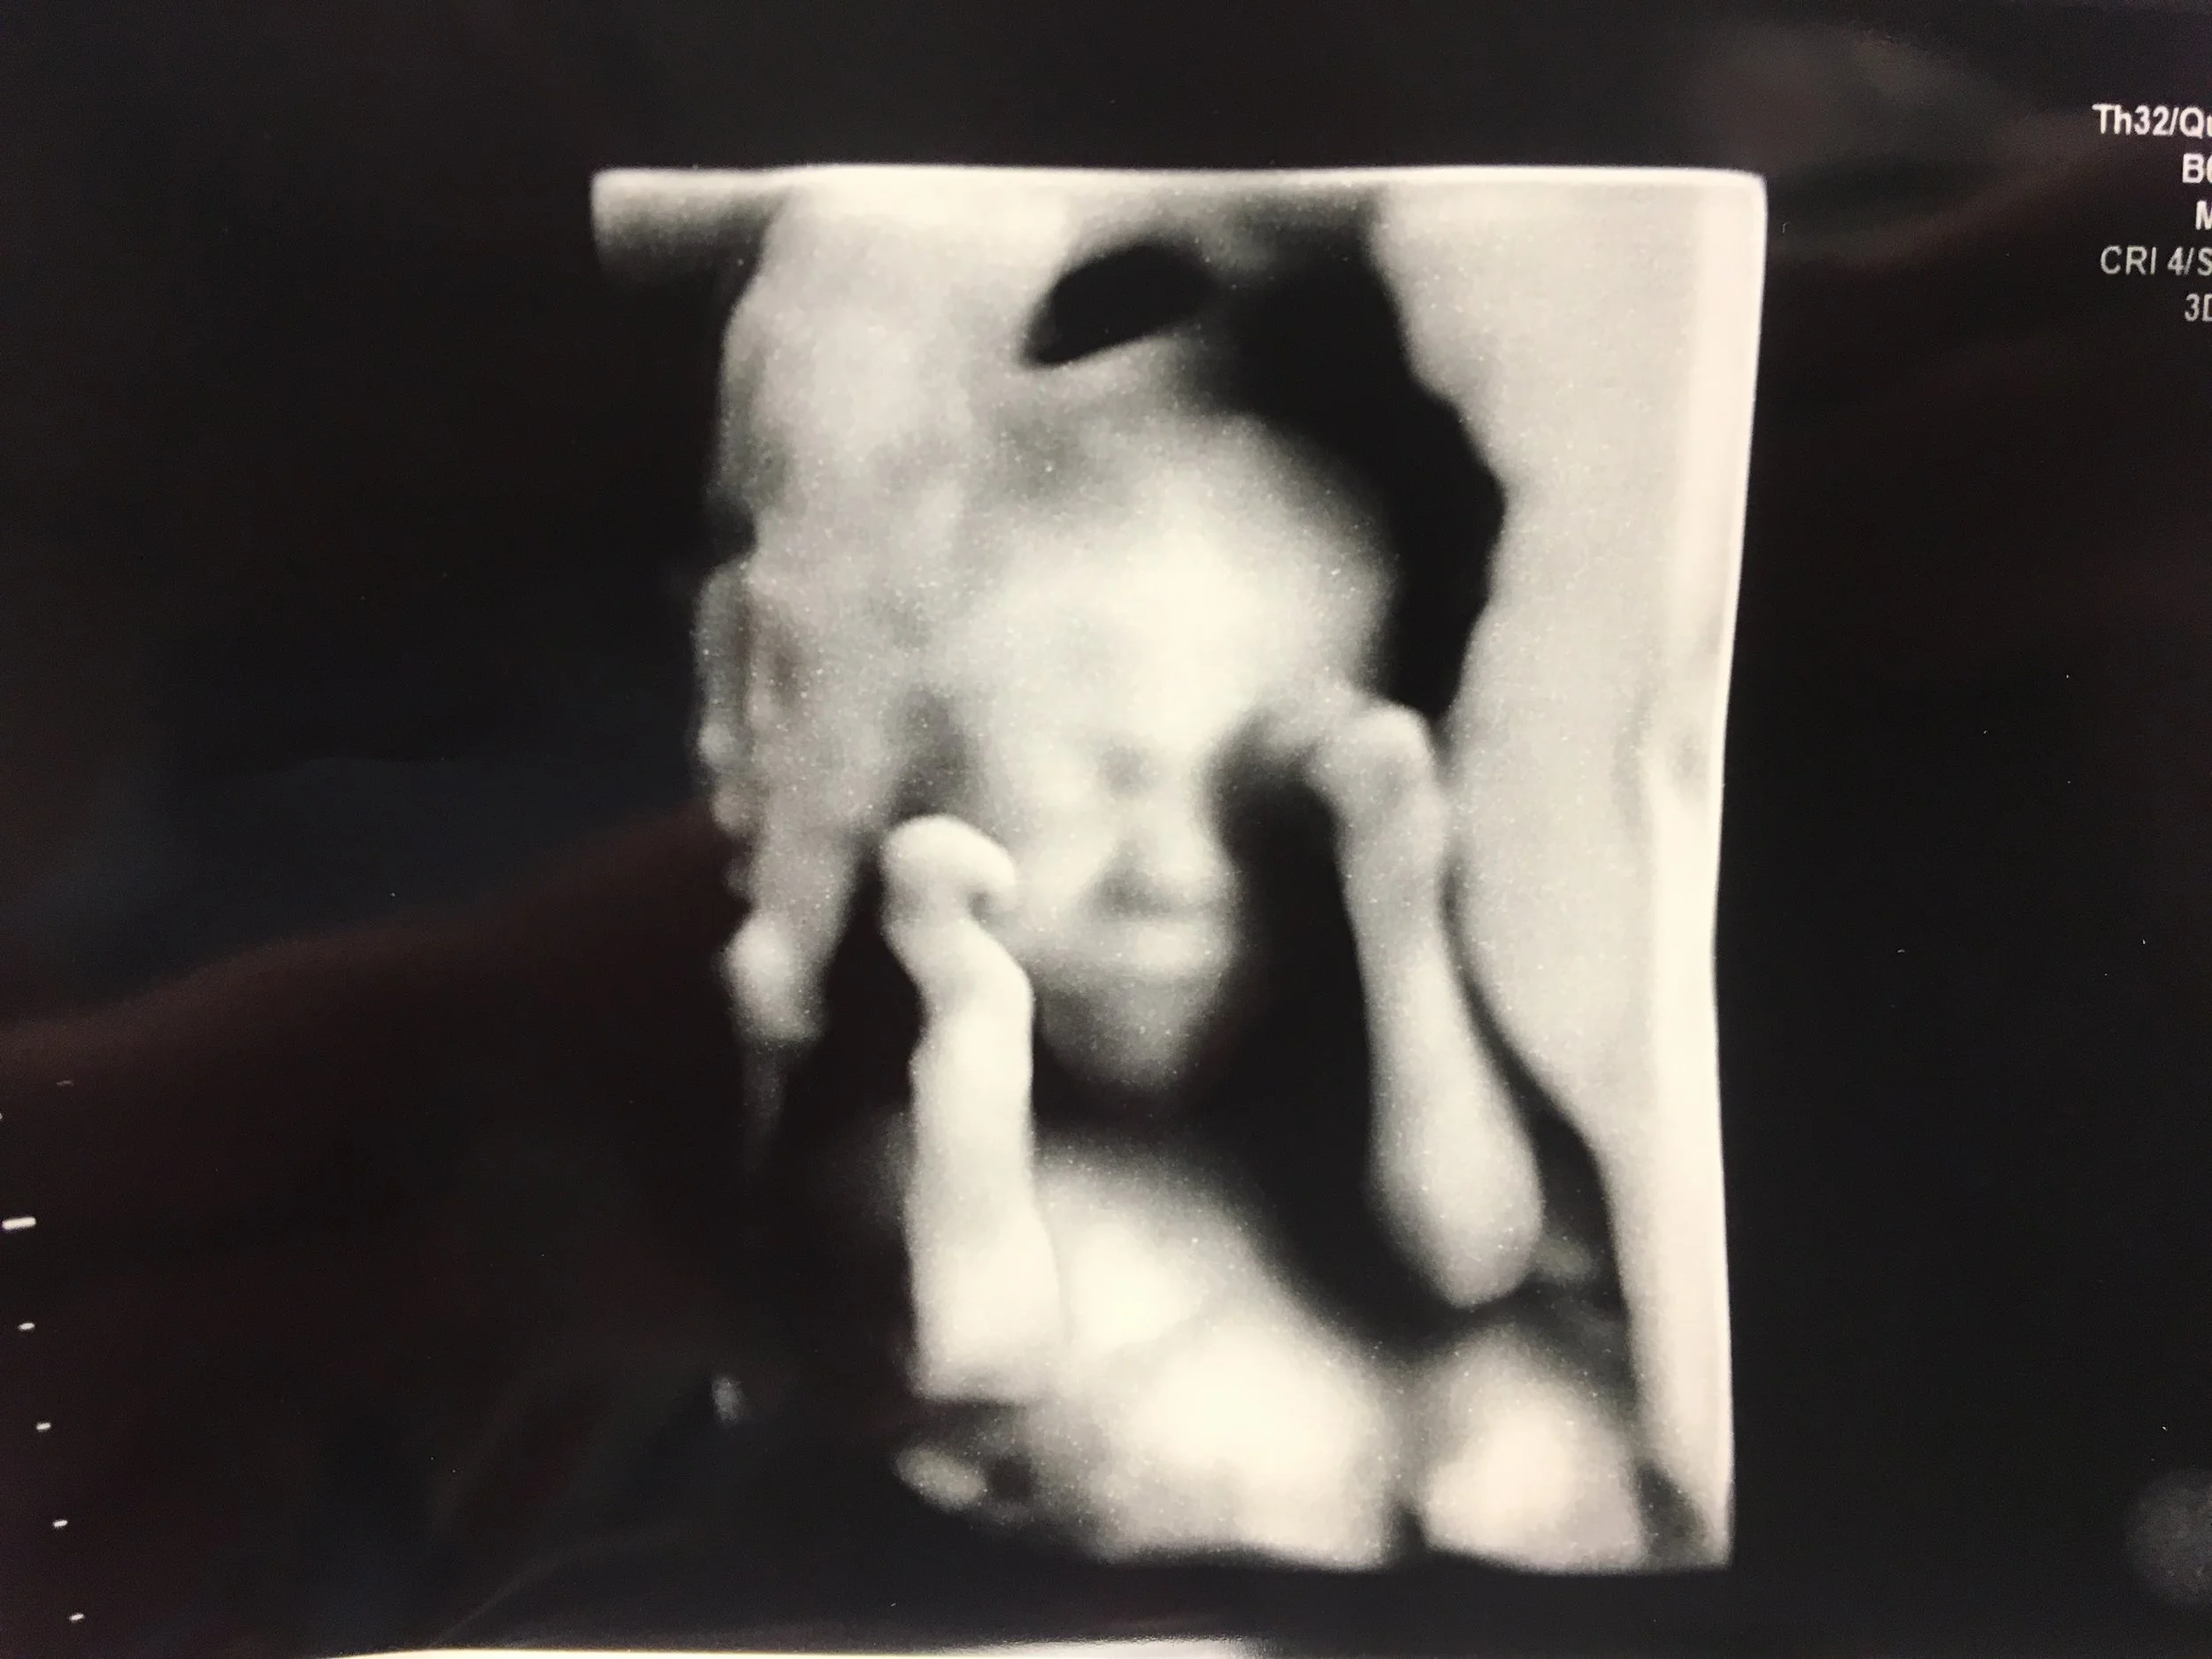

Another cog in the machine of our lives is our exciting pregnancy! Our baby is growing so much! The end of February can't come soon enough. We want to meet the tiny person! We've tried very hard and for a long time to get to this stage in our lives. We've focused so much on getting to this point, now it's really here. It's really going to happen.